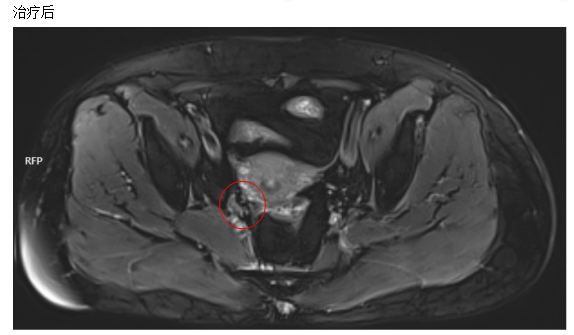

3.治疗方案:

IMRT放射治疗:PTVn:57.5Gy/25Fx,PTV:57.5Gy/25Fx

腔内后装放射治疗+组织间插植治疗:2500cGy/5fx

同步顺铂每周化疗

4. 治疗效果:

经IMRT放射放疗后,宫颈病灶较前部分缩小,宫旁淋巴结消失。